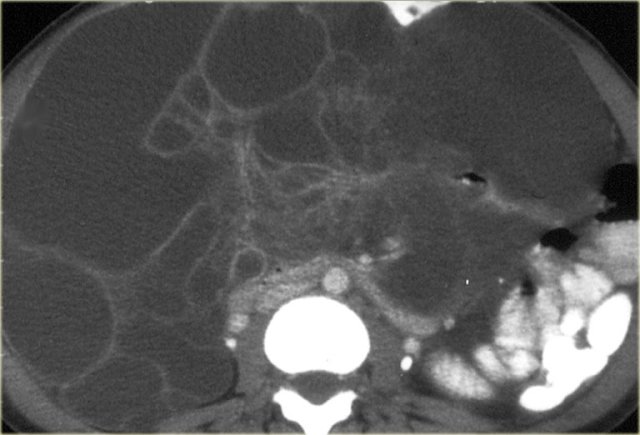

Pseudomyxoma peritonei (2)

On the left another case of pseudomyxoma peritonei.

There is hardly any scalloping of the liver.

Notice the thickened falciform ligament.

There is a mucocele of the appendix (arrow).

This finding is only rarely seen.

There is compression of the mesentery resulting in a thickened cake-like hyperdense mesentery (arrow).

There are also some calcifications.